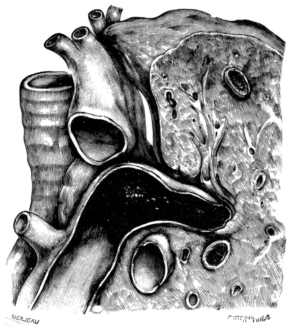

| 23. | A Gravid Uterus in Sagittal Section | 79 |